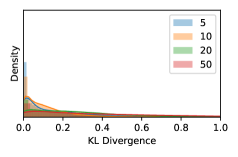

5.1 Distribution of Uncertainty Scores

Distribution of Uncertainty Scores Across Different Severity Levels As explained in Section 3, each uncertainty metric essentially defines an order/ranking among the data points. We conducted an analysis to better understand what data will be assigned high uncertainty under a particular uncertainty metric . Picking out the highest ranked data points (), we calculated the ratio of data points from each SL. Figure 4 summarizes the results as box plots for the Kaggle-DR and the Messidor-2 datasets; additional detailed statistics can be found in Table S.1 in the supplementary materials. From the plot and table, SL1 & SL2 examples account for a higher proportion among the top-ranked uncertain examples across the three ensemble methods. This finding matches our intuition that incipient disease examples (SL1 & SL2) are more likely to be considered uncertain by ensemble methods due to their ambiguity.

Uncertainty Scores on Out-of-Distribution Datasets As an additional experiment, we also tested the performance of the ensemble models on o.o.d. data inputs, which is a classic application of prediction uncertainties [1]. For this task, we produced distribution plots similar to those in Figure 4 for the previous experiment in our supplementary materials. The visualizations for the two o.o.d. image datasets can be found in Figure S.5 for ImageNet and in Figure S.6 for CIFAR-10. The results showed that the majority of o.o.d. data received higher uncertainty scores than in-distribution data for all three ensemble methods, suggesting that these ensemble methods would indeed perform well on o.o.d. detection tasks.

Comparing the three ensemble methods in Figure 4, the stacking ensemble method has the highest ratios of SL1 & SL2 data among the high-uncertainty examples it identified under both mean and var. TTA showed slightly better performance than MC-dropout but still falls behind the stacking ensemble method. Considering the fact that SL0 examples accounted for the majority of the dataset, the stacking ensemble method was much more precise (specific) in selecting truly ambiguous data points that were difficult to classify. From Figure 3, we can also see that the stacking ensemble method greatly outperformed the other two methods in finding false negatives under both mean and var uncertainty metrics.

In contrast, the MC-dropout method showed the worst overall performance among the three, as it can be seen from the high ratios of SL0 examples among the uncertain negatives in Figure 4. The histograms in Figure 2 provides another perspective to look into the phenomenon, where a decent proportion of MC-dropout model’s predictions on SL0 inputs entailed low confidence (far from 0 or 1), which from another angle explained why MC-dropout was less specific in terms of lower FNP; many no-DR inputs (i.e. SL0) were erroneously assigned high uncertainty by MC-dropout models.

It is still an open question why the evaluated MC-dropout networks signaled relatively high uncertainty on SL0 & SL3 & SL4 data that are less likely to be ambiguous. We conjecture that much of the “uncertainty” indicated by disagreement among test-time dropout samples actually reflects the stochastic nature of dropout networks rather than the real decision uncertainty associated with the data. It is worth noting that the MC-dropout model we evaluated was not weak per se; they all achieved above Area Under Curve (AUC) scores on test sets. The weakness of individual test-time samples (which explains their low-confidence predictions on SL0 & SL3 & SL4) might have been hidden when they are aggregated into an ensemble—a well-known advantage of ensemble learning. Our results suggested that the uncertainty information given by implicit ensemble methods such as MC-dropout and TTA might not be as reliable as that from explicit ensemble approaches (e.g., stacking ensembles). Similar findings on MC-dropout can be found in some previous papers [1].

As discussed in Section 5.1 and Section 5.3 in the main paper, the mean metric and the stacking ensemble will have better performance in the precision (specificity) on the ambiguous data. Here, more detailed results are shown in Figures S.3 & S.6 and Table S.1. Figures S.3 & S.4 show the histograms of the uncertainty score for Kaggle-DR and Messidor-2 datasets that are the in-distribution (i.d.) dataset in our experiment and FigureS.5 & S.6 show the histograms for ImageNet and CIFAR-10 datasets, which is the o.o.d. datasets in our experiment. Each group of histograms contains results from the three evaluated ensemble methods (stacking ensemble, MC-dropout and TTA) and the three uncertainty metrics (mean, var and kl). Additional detailed results not displayed in Figure 4 can be found in Table S.1, which shows the proportion of the data of different SLs varies across different . For comparison, we also included in Table S.1 the results from single learners, and the proportions of data of different SLs (before any selection was made).